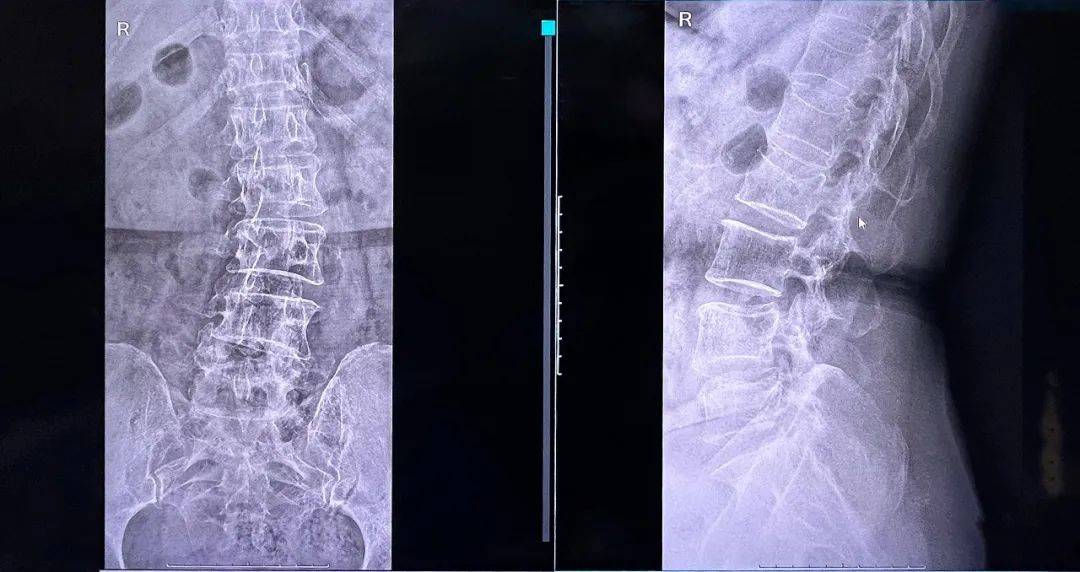

普愛醫(yī)療品牌骨科手術(shù)機(jī)器人的機(jī)械臂憑借高精度導(dǎo)航能力,引導(dǎo)醫(yī)生一次性精準(zhǔn)穿刺,憑借超大內(nèi)傾角度單通道抵達(dá)椎體中央位置,達(dá)到雙通道的骨水泥彌散效果,成功完成兩節(jié)跨節(jié)段椎體的骨水泥注入。

骨水泥在椎體內(nèi)的彌散效果良好,注入量充足、無滲漏。整體手術(shù)時(shí)間縮短,讓患者在本院獲得好的治療。